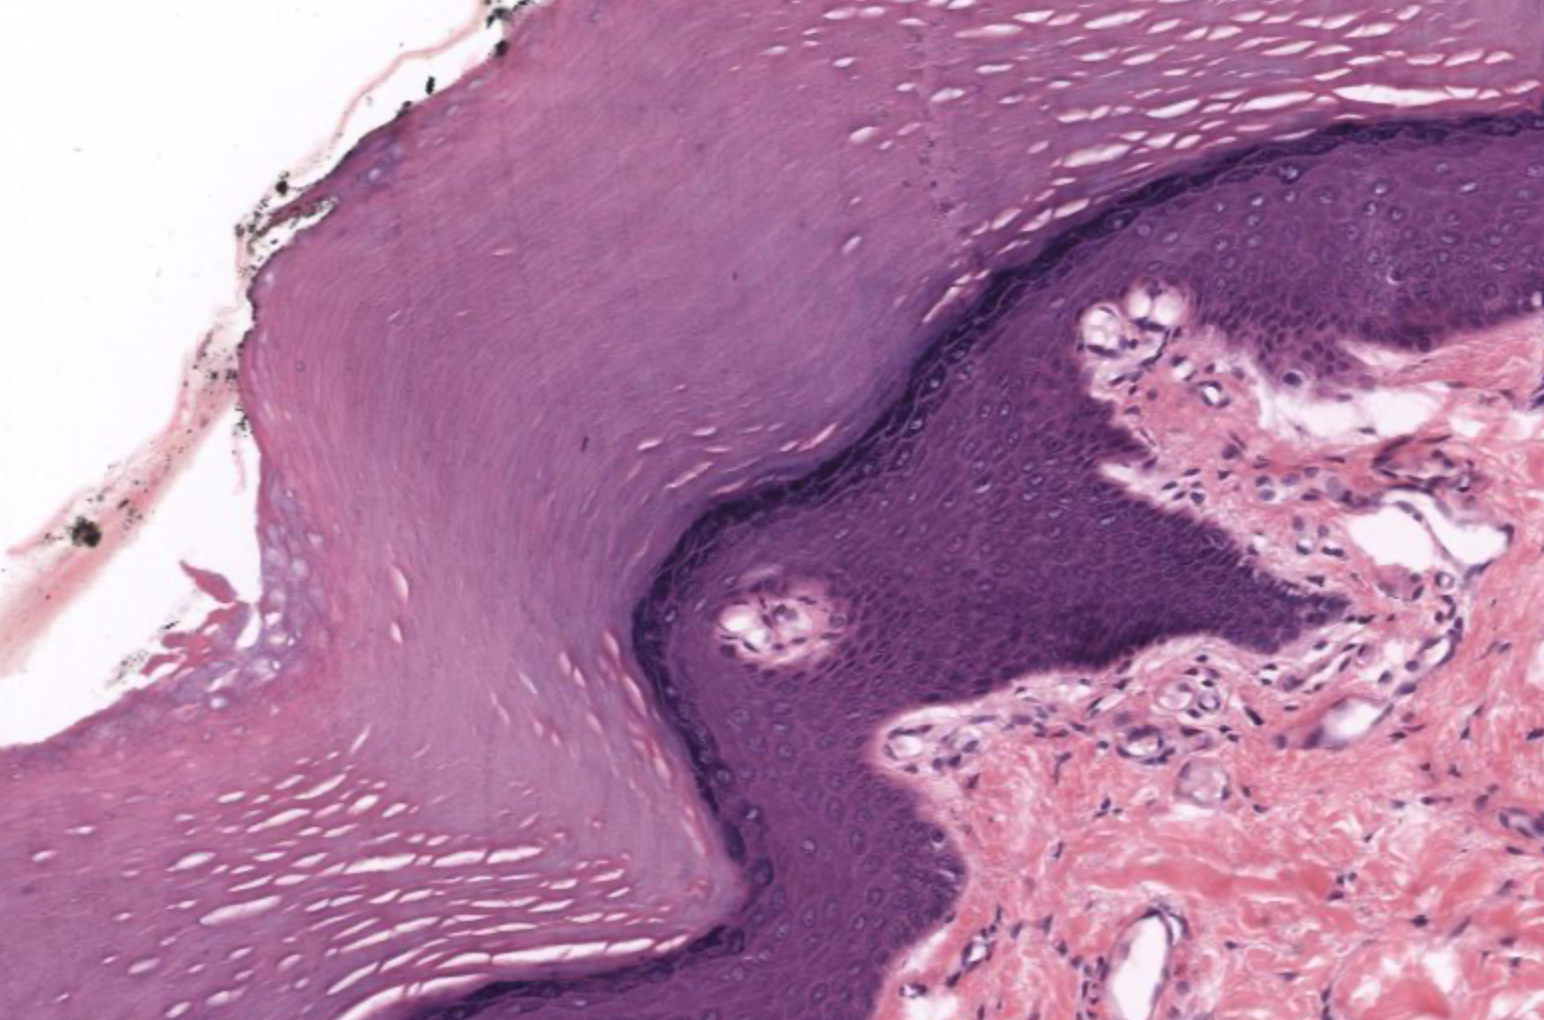

term image

Tissue: nonkeratinized stratified squamous epithelium

Location: anterior surface of cornea

Function:

• protects underlying tissues in areas subject to ABRASION

• surface is exposed to air and is non-keratinized, the epithelium must be kept constantly moist with tears.